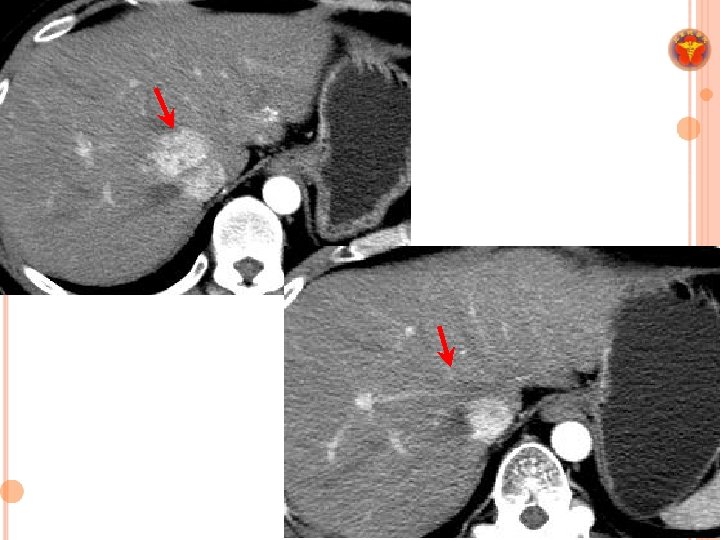

RADIOTHERAPY IN LIVER TUMORS ¢ RT was not standard treatment for liver cancer. ¢ Limitation: * poor radiation tolerance of normal liver * organ motion

PURPOSE ¢ To evaluate the survival outcomes and prognostic factors for patients with BCLC stage C HCC after SABR.

MATERIALS &METHODS ¢ A retrospective cohort study ¢ Between December 2007 and July 2015 ¢ BCLC stage C disease ¢ Child-Turcotte-Pugh class A–B